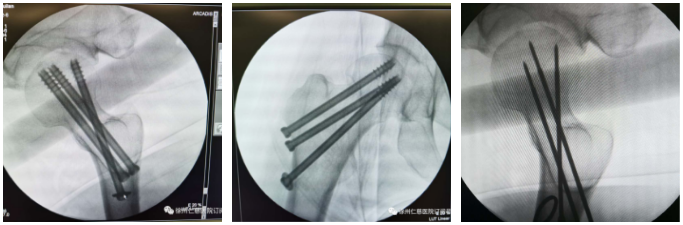

手术中,患者仰卧在骨科牵引床上,通过手法牵引复位骨折,C型臂透视下见骨折对位对线良好,将复位后的正侧位图像输至骨科手术机器人主控平台,手术医生在主控平台上进行置钉规划,将指令传输给机器人手臂,而后机器人手臂自动运行至需要置钉的位置,插入套筒,沿套筒打入导针,钻孔,依次把3枚空心螺钉置入。C型臂透视再次验证,确认螺钉位置与规划一致。这样,最困难最危险的步骤完成了。

以前没有骨科机器人的情况下,这样大角度交叉打钉,是几乎无法实现的。

“以前没有手术机器人,骨科手术基本上要求患者在C型臂下反复透视,才能让医生更好地找准进针位置。误差比较大,有可能需要反复透视,反复置钉,对骨头的损伤也比较大。现在,有了骨科手术机器人帮忙,置钉准确,基本上没有反复的动作,透视也减少了。‘天玑’的‘一臂之力’使手术定位精度达到0.8毫米,可减少术中辐射70%以上,并具有提高手术效率、减少失血量和减少术中组织创伤等优点。”关节科蒋守海主任说。